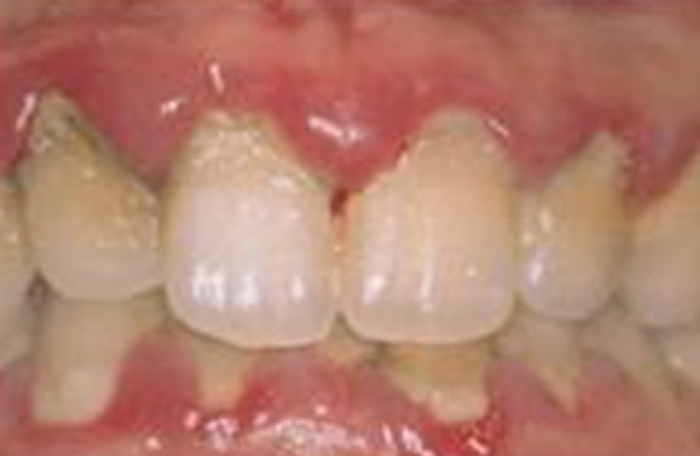

重度歯肉炎の症状

プロービングを行わなくても自然出血、発赤、腫脹が特徴です。

仮性ポケットが形成されます。歯冠側に歯肉の高さが増大します。

そして最悪の場合、歯が抜けてしまうこともあります。